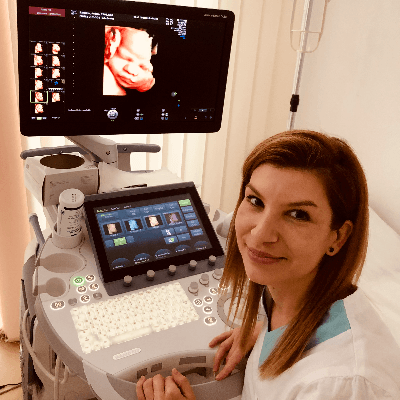

Crismaru Iulia Romania Physician